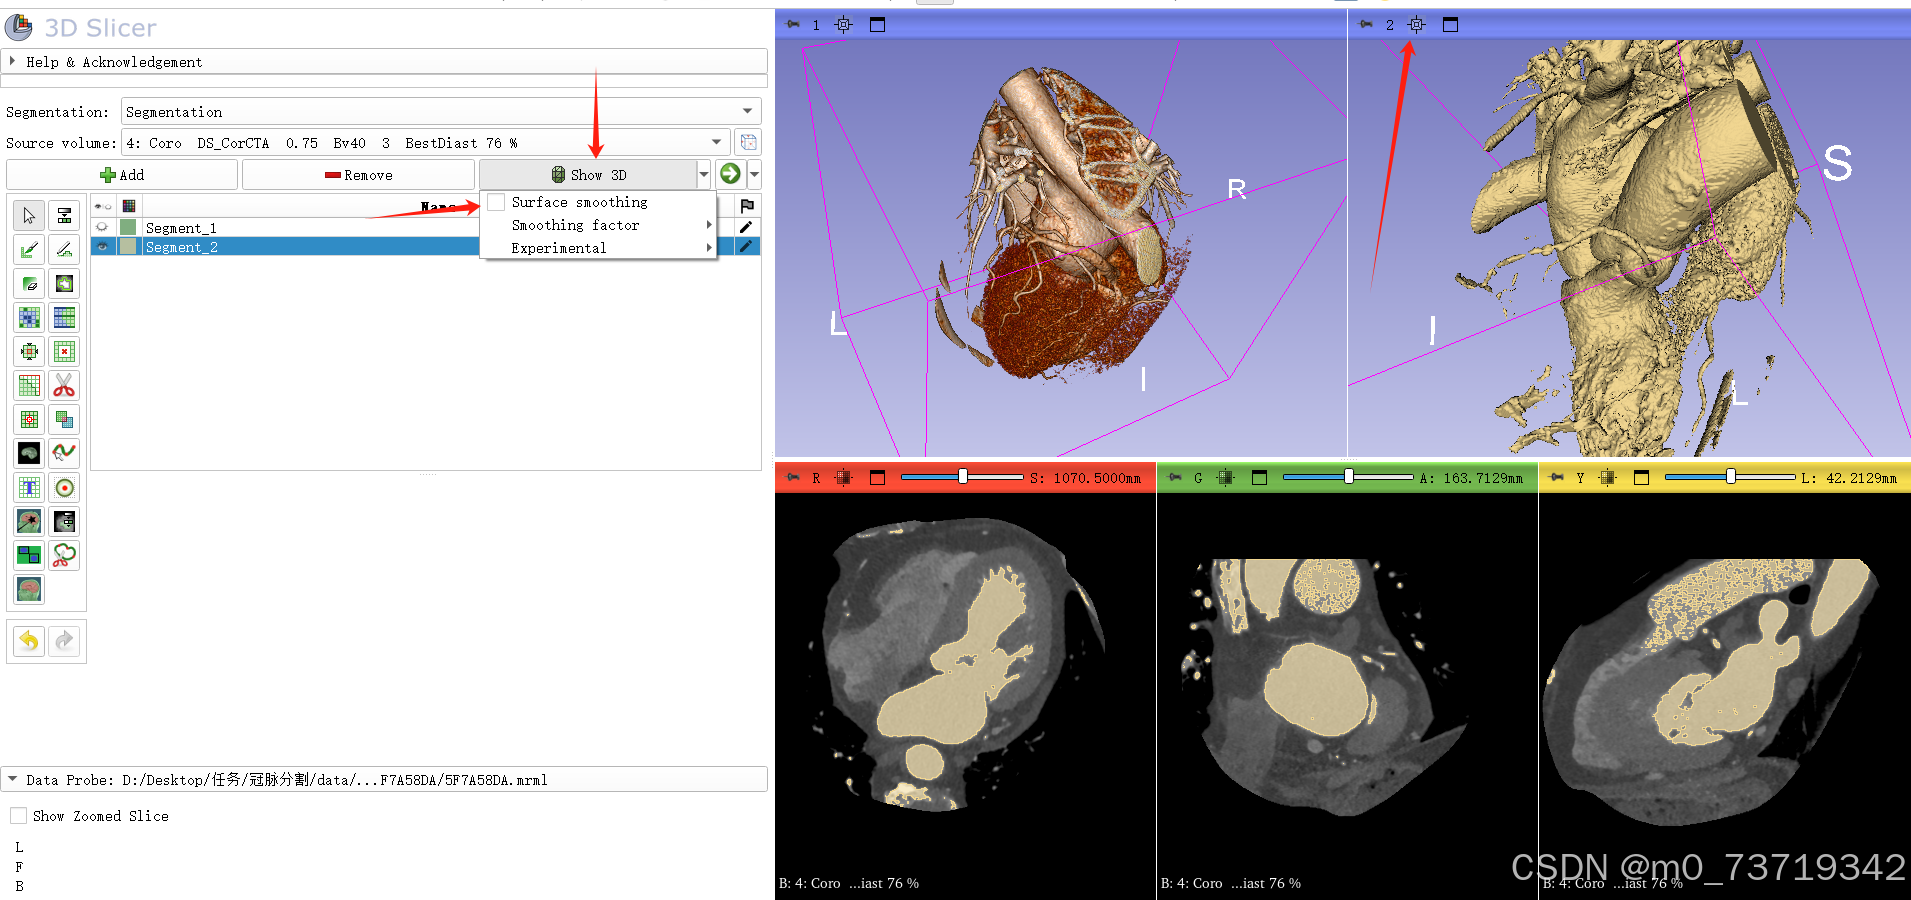

在三维视图中可观看如下

5.三维球刷标出冠脉位置

新建标注3

依次点击如下按钮

在三维视图中拖拉球刷对冠脉进行标注(shift+鼠标滚轮调整球刷大小)

问题:显卡问题使用三维球刷标注卡顿

解决方法1:在标注之前先remove掉三维图像中的小噪点,显卡计算量减小,卡顿减轻